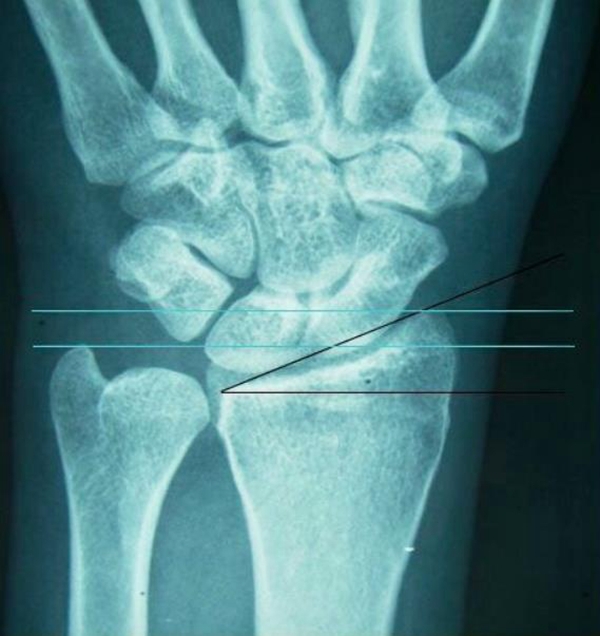

4、桡骨远端骨折合并下尺桡关节(DRUJ)分离:

绝大部分桡骨远端复位后DRUJ可自行复位。若桡骨远端复位后DRUJ仍然分离,采取手法挤压复位,应用外支架的侧杆固定。

图7 桡骨远端骨折合并下尺关节(DRUJ)分离,加用侧杆固定